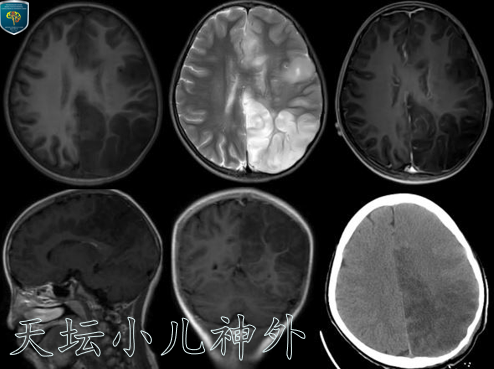

图2患儿2020年8月复查CT/MR显示病变范围扩大,波及左侧丘脑,右下肢出现乏力症状